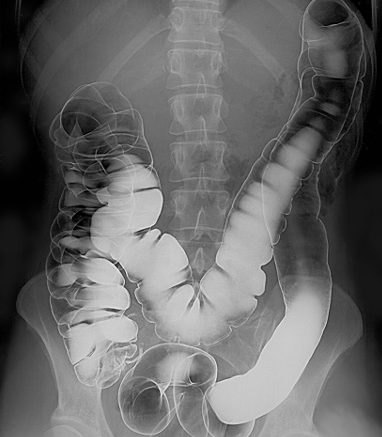

Intestinal tract barium enema

By Glitzy queen00 at English Wikipedia., Public domain, via Wikimedia Commons

A barium enema is a rectal injection of barium contrast. This coats the lining of the colon and rectum and X-ray films are obtained under fluoroscopic control. Air introduced into the large bowel may be used to give a double-contrast technique. Barium enemas are performed much less often than in the past because of the increasing use of colonoscopy and CT colonography.

Barium is run into the colon under gravity and radiographs are taken. Air is also then introduced into the rectum for a double-contrast barium enema.